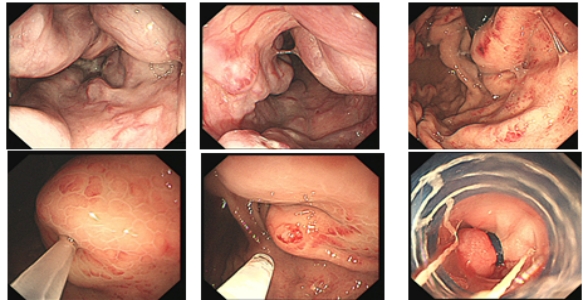

胃内粘膜下隆起,术前结合我科超声内镜,诊断考虑异位胰腺。

89岁高龄患者,诊断胃早期肿瘤,行胃镜下微创治疗(ESD),创伤小,恢复快,保留完整器官。

行内镜粘膜下挖出术(ESE)治疗,术后行荷包缝合,杜绝术后并发症。

胃内粘膜下隆起,术前超声提示来源于固有肌层,术前判断需胃壁全层切除。

术中所见与术前判断相符,行内镜全层切除术EFTR,术后严密封闭创面,患者2日后安全出院,术后病理诊断胃间质瘤。

结肠腺瘤的ESD手术

十二指肠溃疡降段早癌的内镜粘膜剥离手术治疗(ESD)

直肠巨大侧向发育型肿瘤,内镜下完整切除(ESD),术后病理证实粘膜内癌,不需追加治疗,达到治愈目的,保留正常器官,避免外科手术。

胃内4x4cm粘膜下隆起,胃镜下完整切除(ESE),术后病理证实平滑肌瘤,保留胃正常组织结构。

内镜手术展示

: